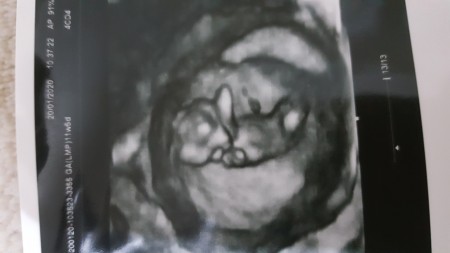

Mrb Kızlar 11+5 günlükde hamileyim dün doktora gittim cinsiyet için erken dedi ama çıkıntısı yok kıza benziyor dedi haftaya gel kesin bisey söylerim dedi sizde durumlar nasıl oldu? :)

Evet ;) ama pek bisey belli olmuyor

Ya canım birde bende doktor dedi gelişimi bir hafta önde normalde 11+5 ama uzunluğu falan 12+4 lük gibi o yüzden cinsiyette oluşmuş mudr diye düşündüm ama sadce tahmin etti